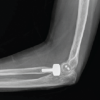

This prospective study was carried out between April 2022 and April 2024 after obtaining clearance from the Institutional Ethics Committee, among patients from the age group of 18–80 years who underwent dorsal bridge plate fixation for distal radius fracture at the Orthopedic Department, Government Medical College Kannur, Kerala, from April 2022 to April 2023 and followed up between April 2023 and April 2024. Patients who did not consent to the study, with open distal radius fractures or with distal radius fractures fixed with volar buttress plates, k wire, or external fixators were excluded from the study. A consecutive sampling method was used to identify the test subjects. The subjects were categorized into two groups based on distal fixation of the dorsal bridge plate at the second or third metacarpals. Patients with distal radius fractures (Fig. 1) underwent surgery either within 24 h or within a week of their injury. Suture removal was done on the 12th day following surgery (Fig. 2-4). Implant removal was done 6 weeks postoperatively after radio graphically ensuring that adequate union had taken place (Fig. 5&6). Following this, physiotherapy for wrist movement was initiated. Patients were assessed during monthly follow-ups of surgery based on the stiffness, range of movements (Fig. 7&8) and tendon entrapment using the Green and O’Brien Score. The data collected was entered in Excel sheets and statistical analysis was done using SPSS version 26. Data were shown as mean ± standard deviation.